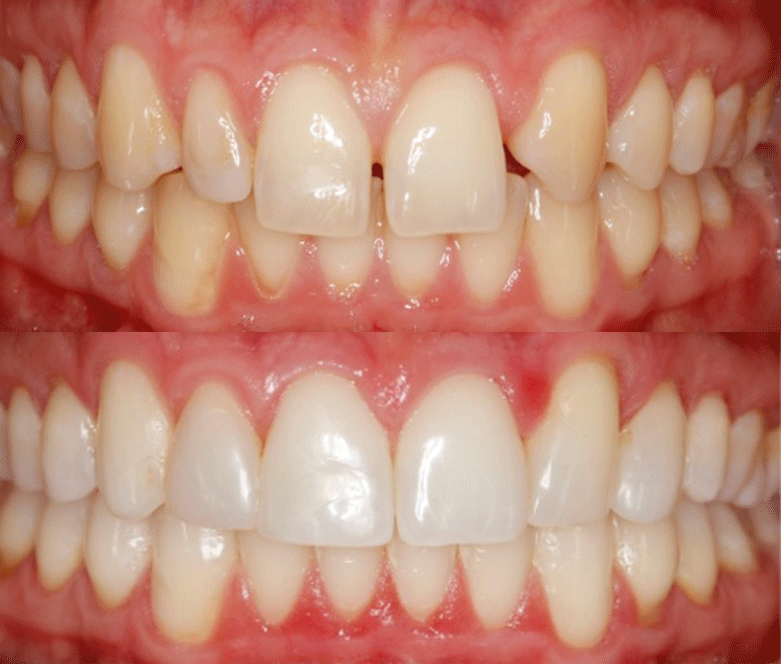

We will then map out a complete treatment plan showing the gradual realignment that will reposition the teeth from their current position to where they will be when the treatment is complete.